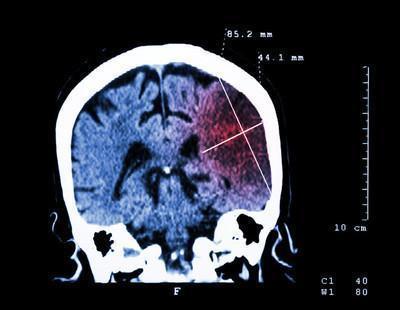

3、造成脑梗高血脂同时会伴有血液中的胆固醇会增加,然后它会在血管中积聚,这将使血管中容易形成动脉粥样硬化斑块,硬化的斑块会使患者的血管变窄,并导致血液流动缓慢,然后诱发脑梗。